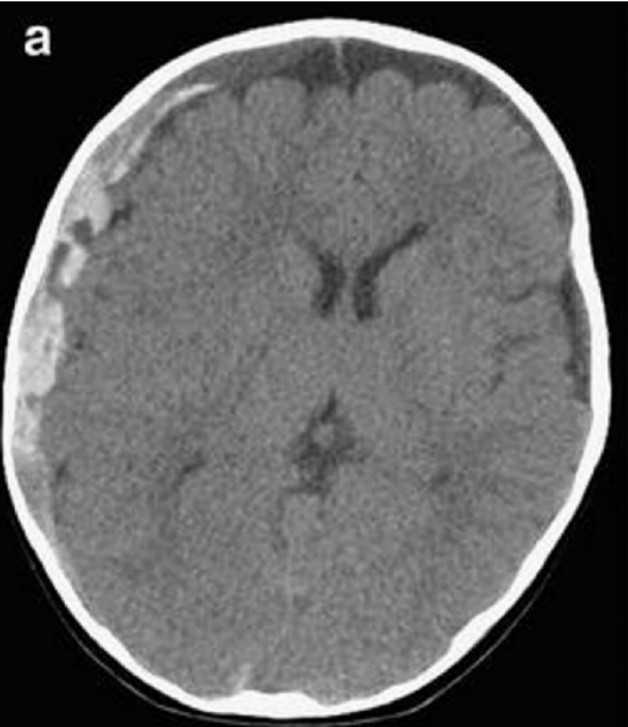

Head injury

A 27-year-old man presents following an assault. He had a GCS of 5 at the scene and has been intubated …